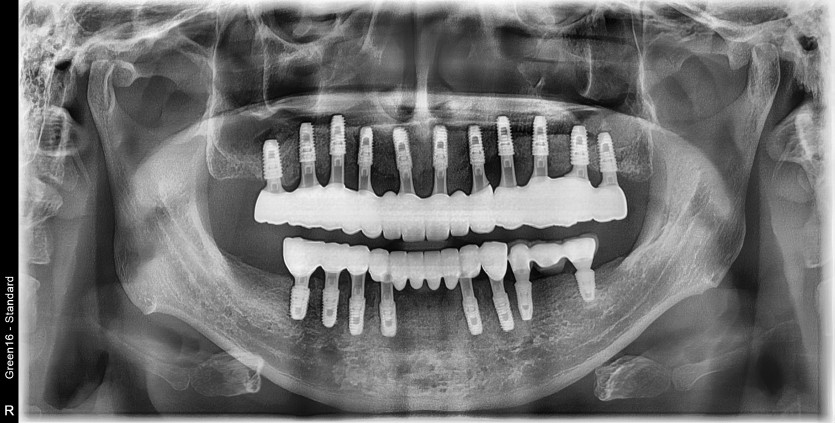

만 41세 전체 임플란트 증례

16개의 임플란트로 완성하였습니다.